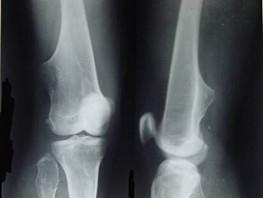

问题 女,15岁,大腿远端可摸到肿块,无明显疼痛,请结合研提供图像,选择最佳答案 ( )

选项 A、骨瘤 B、骨软骨瘤 C、软骨瘤 D、骨肉瘤 E、骨质增生

答案 B